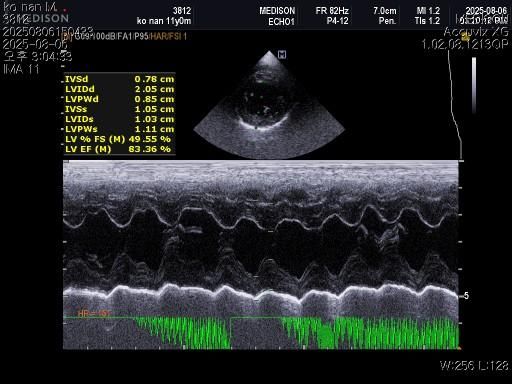

1) 혈액검사와 엑스레이 그리고 초음파상 혈뇨의 원인이 나타나지가 않는지 궁금합니다.

2) 그리고 전립선 비대가 있는지도 없는지 여부가 궁금합니다.